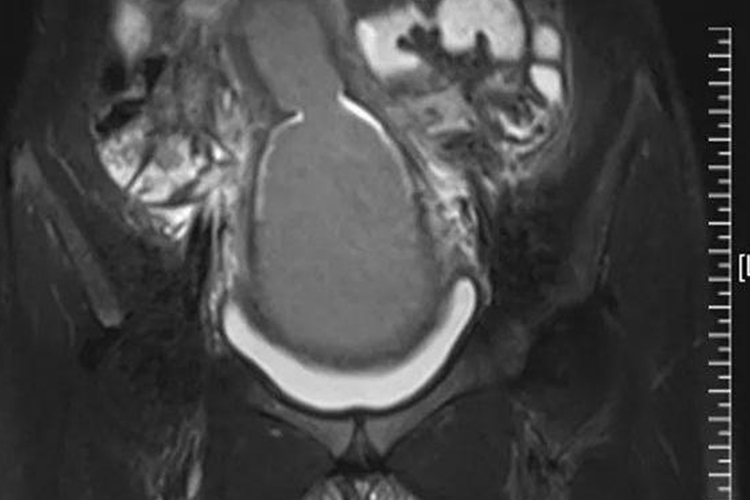

盆腔磁共振成像:常作为进一步检查的手段,对宫颈、子宫的结构检查得更为精确,尤其对于存在功能内膜但发育不良子宫的患者,具有精确诊断的价值。